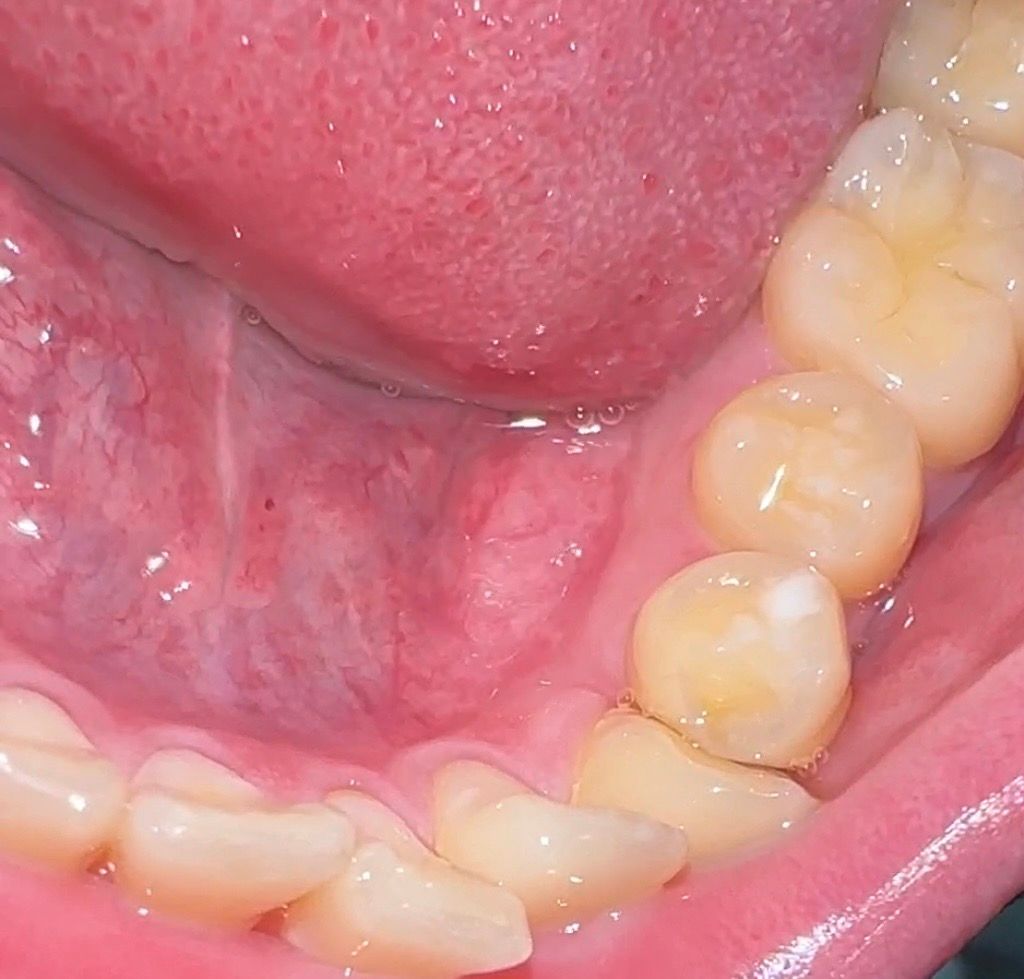

작은어금니 씹는면이 많이 닳은것같아요

잘때 이 악무는 습관때문에 마모가 생긴거같은데

이정도면 심한편일까요??

조금 시린느낌이 드는데 어떻게해야할까요

사진으로도 마모가 진행된것으로 보입니다.

사진상으로는 마모정도가 정확히 보이지는 않으나, 시린느낌이 드는 경우에는 크랙이나, 범랑질 손상의 가능성이 있습니다. 시린증상지속시에는 검사를 받고 확인해보길 권합니다.

약간 마모가 된 곳이 보이기는 합니다. 시린이 치약을 쓰는 것은 도움이 될 수도 있고 아닐수도 있습니다.